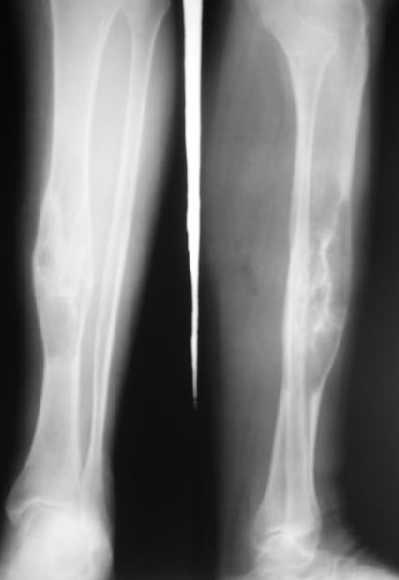

"При его рассмотрении с рентгенологом и морфологом сошлись, что это не фиброзная дисплазия, что было первым предположением по рентгенограммам. В полости было и мягкотканое образование. Окончательно заключение дадут через несколько дней"

По локализации и по характреру опухоли мало напоминает остеобластому, может, представленные биопсийные материалы адамантиномы помогут вашим морфологам дифференцировать опухоль (Basiloid cells, pseudoglandular pattern and peripheral palisading)

Недавно на нашей ежемесячной Morbidity&Mortality

conference мы разбирали похожий случай, ложный сустав большеберцовой кости после резекции опухоли.

К нашему онкологу-ортопеду обратился больной с жалобами на боли в голени, из рассказа - год назад была сделана биопсия большеберцовой кости, но название заболевания "не запомнил”.

Оперирован в военном госпитале с заменой сегмента

аллокостью большеберцовой кости и после демобилизации явился для постоянного наблюдения по месту жительства.

В литературе "A Classic Adamantinoma Arising from

Osteofibrous Displasialike Adamantinoma in the Lower Leg: A case report and Review of the Literature похожие снимки.

Наши имели проблему со сращением, пришлось им сделать динамизацию, дополнительную аутопластику.

Снимки представлены.